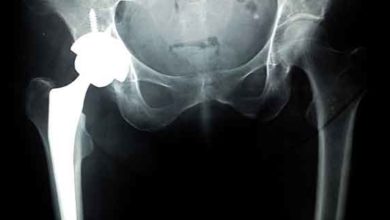

Total kalça protezi rehabilitasyonu

Kalça ekleminin ilerleyen dejenerasyonuna koksartroz adı verilir. Koksartroz kalça ekleminde ağrı ve hareket kısıtlılığı ile karakterize dejeneratif bir hastalıktır. Hastalığın…